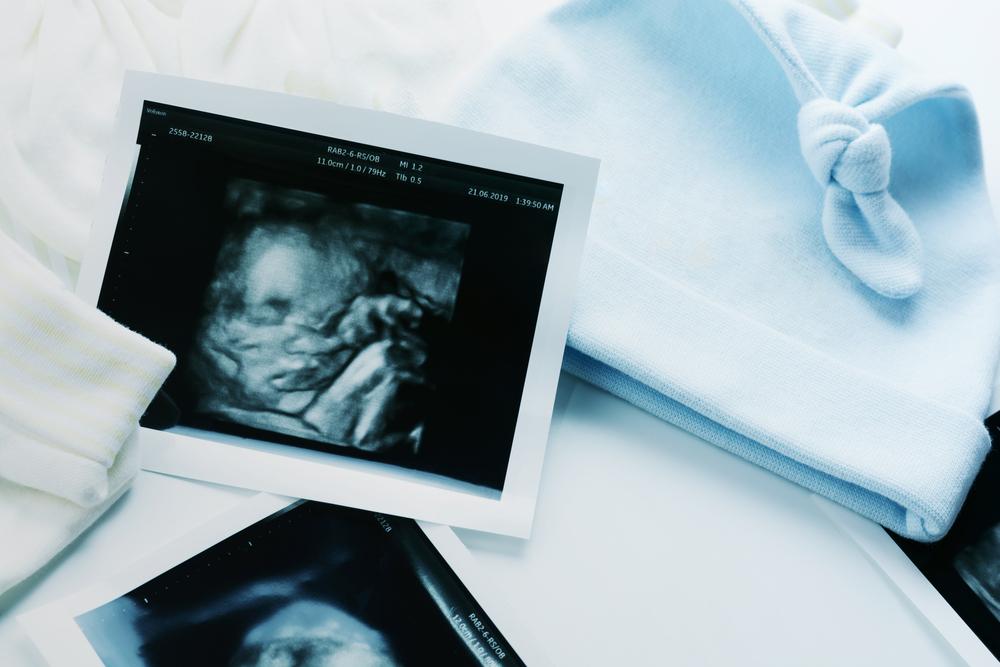

Siêu âm hình thái học là kỹ thuật siêu âm cho phép quan sát hình ảnh của thai nhi trong bụng mẹ. Quá trình quét có thể kiểm tra được kích thước thai nhi, hình dáng bên ngoài lẫn các cơ quan bên trong cơ thể của em bé.

Kỹ thuật siêu âm này có thể được thực hiện bất cứ lúc nào trong khoảng từ tuần 18 đến 22 của thai kỳ nhưng lý tưởng nhất là khi thai được 20 tuần. Nguyên nhân là vì ở giai đoạn này, thai nhi đã phát triển và hoàn thiện các cơ quan bên ngoài lẫn bên trong cơ thể nên rất dễ quan sát khi quét siêu âm. Việc tiến hành siêu âm hình thái học đúng thời điểm sẽ giúp bác sĩ phát hiện được các bất thường nếu có. Từ kết quả siêu âm, bác sĩ có thể tư vấn cho mẹ bầu hướng xử lý hoặc cách chăm sóc thai kỳ phù hợp nhất.